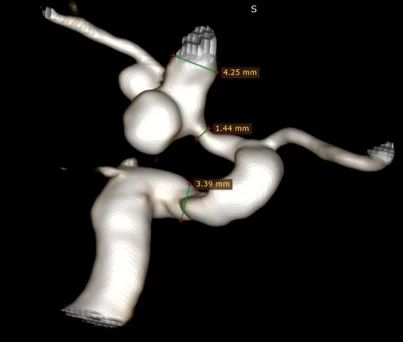

4. 3D重建后我们可以看到,这是一个宽颈的分叶状动脉瘤,载瘤动脉正常管径大约4mm左右,但狭窄段最细仅有1mm多,支架的选择至关重要。

3D重建与测量